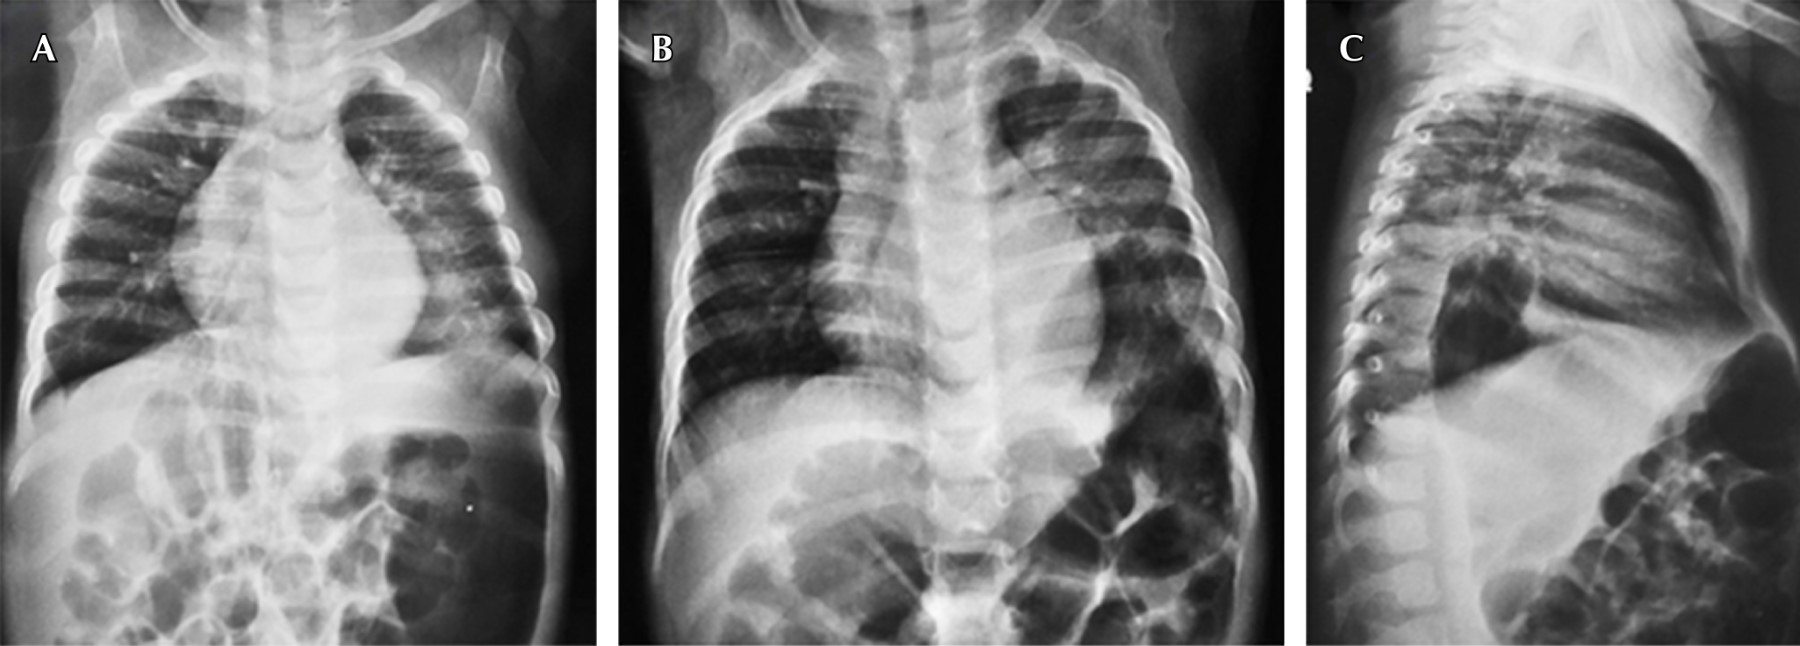

Hospitalizada en cuatro ocasiones desde los siete meses por dificultad respiratoria catalogada como neumonía de la comunidad (Figura 1A). A la exploración física: frecuencia cardiaca 162 lpm, respiración de 45 rpm, saturación: 89%. Fenotipo Down (braquicefalia, epicanto, cuello corto, puente nasal aplanado, protrusión lingual pliegue palmar), campos pulmonares con hipoventilado en hemitórax izquierdo, así como crepitantes en base pulmonar izquierda, abdomen blando depresible. Pruebas de laboratorio: TSH 48 mU/l, T4 0.5 ng/dl, radiografía de tórax revela niveles hidroaéreos, así como asa intestinal en el espacio retroesternal (Figura 1B y 1C). Medio de contraste demostrando imagen de asa intestinal en cavidad torácica (Figura 2). El Servicio de Cirugía reportó saco herniario con presencia de estómago y bazo, defecto de 4 cm de diámetro aproximadamente.

Figura 1